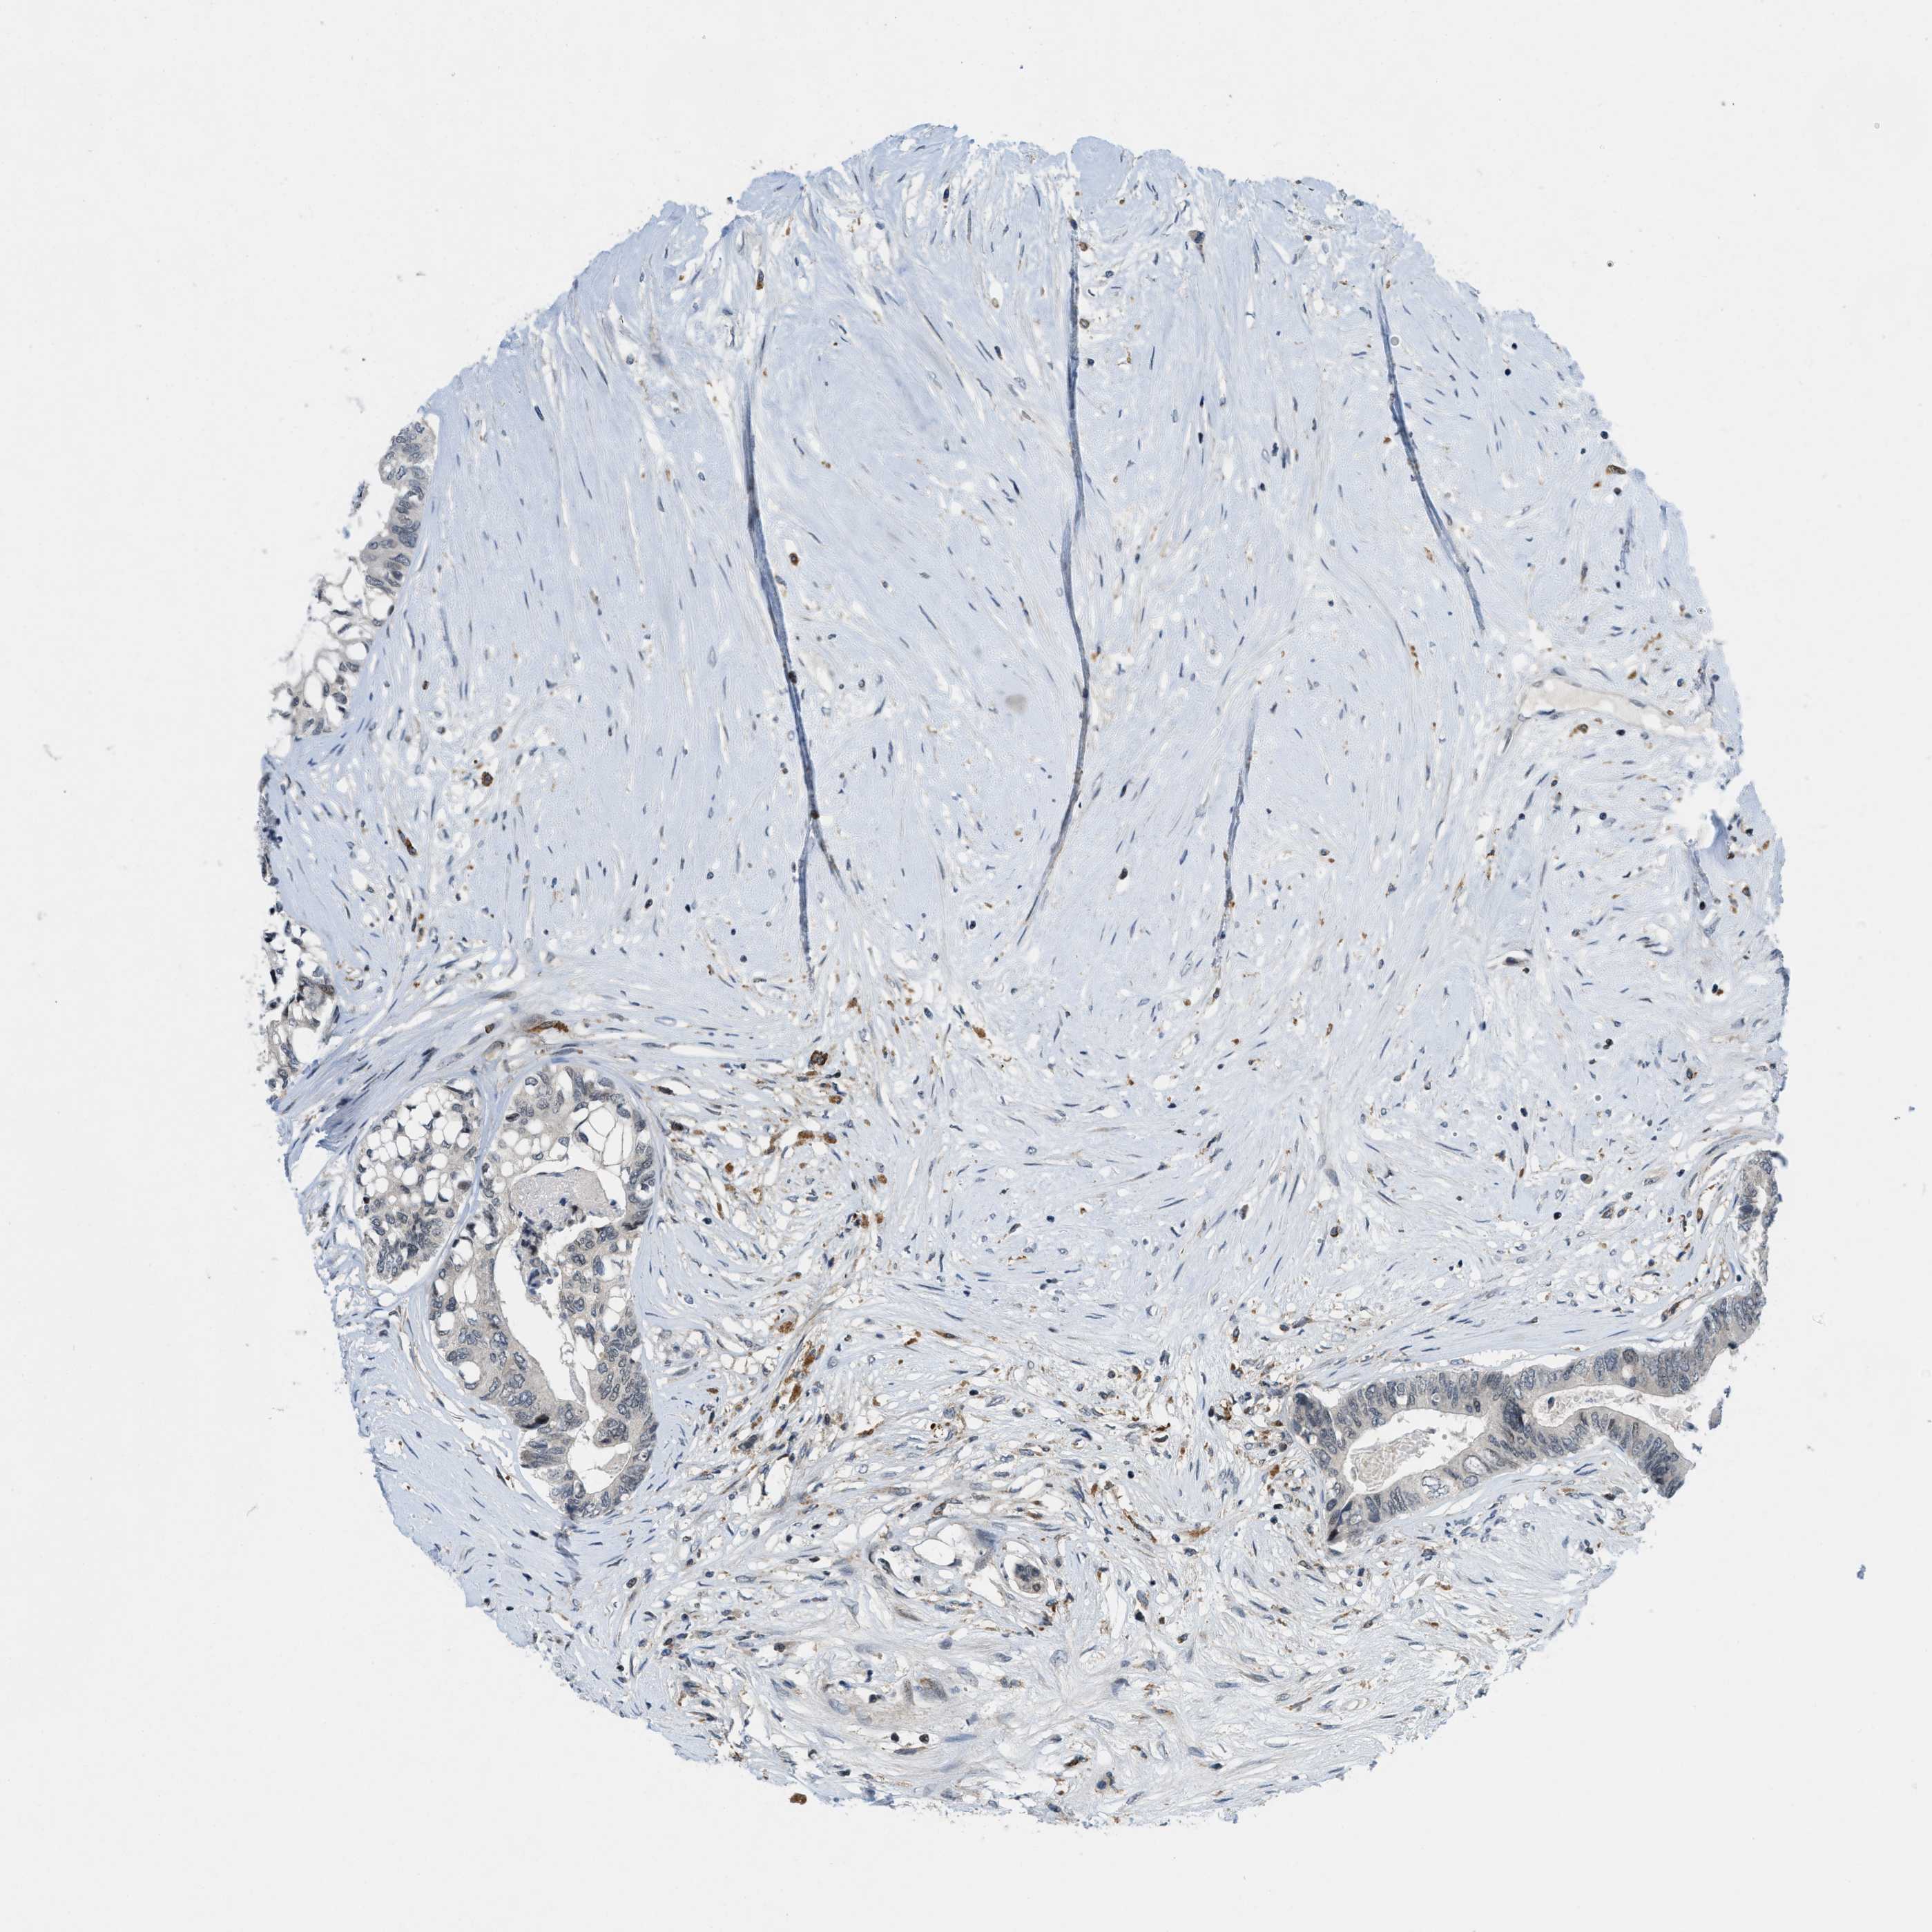

CANCER COLORECTAL CANCER Show tissue menu

Colorectal cancer

Human cancer